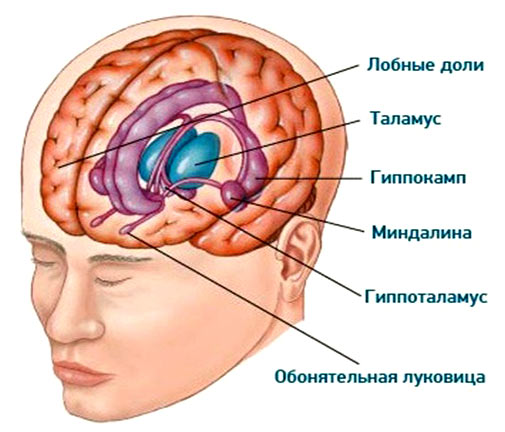

2) Лимбическая система – также является одной из самых старых частей мозга, хотя и более «новая» по сравнению с ретикулярной формацией с точки зрения эволюционной истории, так как связана с более сложными социальными взаимодействиями и когнитивными способностями. Тоже занимает небольшую часть общего объема мозга. Хорошо развита у млекопитающих, где она участвует в процессах обучения, памяти и эмоционального поведения. Напрямую влияет на такие черты личности, как эмоциональная стабильность, реакция на стресс и взаимоотношения с другими людьми. Помогает усиливать воспоминания на основе эмоциональной значимости, регулирует гормоны, которые влияют на настроение и эмоции, играет ключевую роль в формировании новых воспоминаний и обучения, важна для пространственной памяти и переноса информации в долговременную память.

3) Префронтальная кора – составляет около 10% объема всего головного мозга и является специализированной областью внутри структуры неокортекса. Ответственна за регулирование сложных когнитивных процессов, включая планирование и принятие решений, социальное взаимодействие и самоконтроль. Связана с чертами личности, такими как ответственность, импульсивность и адаптивность. Участвует в удержание и манипулирование информацией в коротком временном промежутке для выполнения когнитивных задач.

4) Теменные доли – занимают около 5% объема головного мозга и также являются частью неокортекса. Важны в ориентации в пространстве, обработке сенсорных сигналов и интеграции информации для восприятия и понимания окружающего мира. Это может влиять на такие аспекты личности, как открытость к новому опыту и способность к адаптации. Помогает управлять вниманием и участвует в хранении семантической памяти.

5) Височные доли – часть неокортекса ответственная за обработку слуховой информации, понимание языка, визуализацию и восприятие эмоций, формирование воспоминаний.